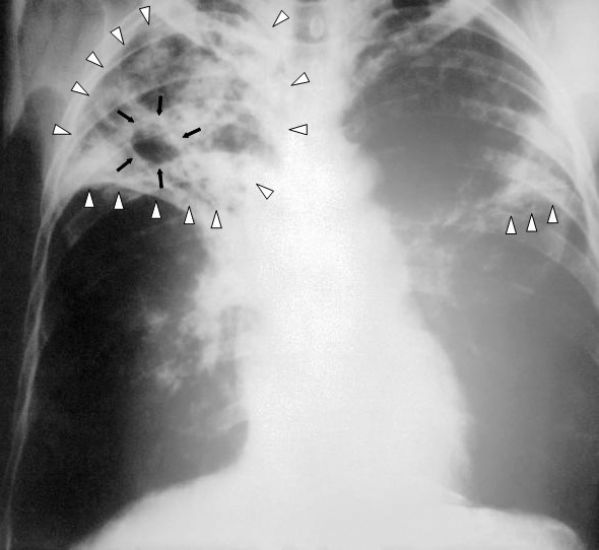

A enfermidade é causada, como já dito, pelo Bacilo de Koch, uma bactéria que afeta principalmente os pulmões, podendo atingir outras áreas do corpo.